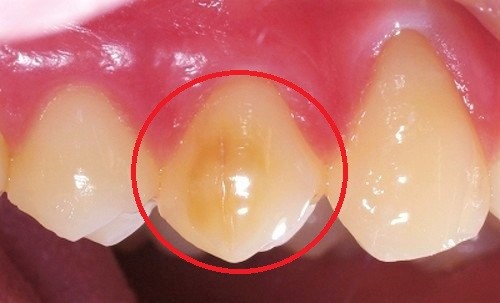

歯の表面はエナメル質という、人体の中で最も硬いもので覆われています。

しかし、そのエナメル質が何らかの原因で 先天的に影響を受け、

上手く作られなかった歯のことを、エナメル質形成不全といいます。

エナメル質形成不全の歯は歯質が欠けていたり、歯の石灰化が不全のため

歯の表面がザラザラしていて、汚れも溜まりやすいため、他の健康な歯に比べて

むし歯になるリスクが高く、一旦むし歯になると進行も早いです。